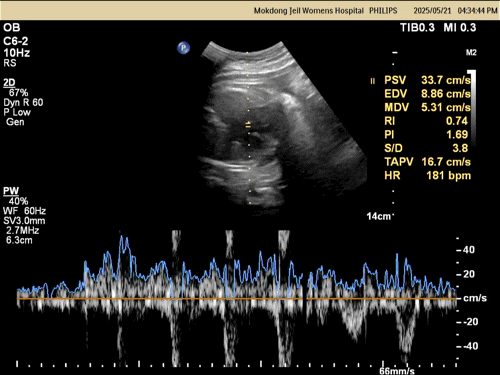

2025.05.20(36주) 어제 새벽부터 배가 아프더니 점심까지 계속 배가 아팠다. 또 변비 때문인 것 같긴 한데....